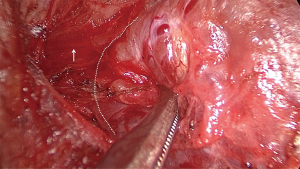

Further dissection was performed on the tracheal side to cut off the Berry ligament and release the thyroid toward the opposite side. The tissue between the superior pole of the thyroid gland and the strap muscles was further dissected to expose the cricothyroid muscle. The dissection was performed laterally on the superior pole of the thyroid with intermittent 3 mA current stimulation to detect the EBSLN (12). A positive standard was based on electromyographic signals or the contraction of the entire cricothyroid muscle (13). Further exploration was performed along the area with the strongest electromyographic response, and upon locating a suspicious nerve, the current was adjusted to 1 mA for confirmation of the nerve (Figure 5).

All patients underwent successful endoscopic surgery without conversion to open surgery. EBSLN dissection was performed in 46 of the 48 patients. In two of the patients no EBSLN dissection was completed, attempts were made to identify the nerve, the procedures took approximately 10 minutes each, but the nerve could not be located. To avoid potential damage from further manipulation, further exploration for the nerve was abandoned. Of the dissections, 25 were performed during left thyroidectomy and 23 were performed during right thyroidectomy. Additionally, 42 (87.5%) patients had positive electromyographic signals. Among the patients, 3 were classified as Cernea type 1, 41 as type 2a, and 2 as type 2b (15). Additionally, one patient had a nerve that ran deep to the inferior pharyngeal constrictor muscle (16) (Figure 6).

After the location of the EBSLN was confirmed, we followed its course slightly upward for further dissection and confirmed that the nerve was safely distanced before using an ultrasonic scalpel to coagulate the blood vessels at the superior pole of the thyroid. We were cautious to avoid injuring the swallowing muscles and the cricothyroid muscle. In one patient, despite repeated exploration in the area of the superior pole, the nerve tissue could not be clearly identified; however, twitching of the cricothyroid muscle was detected at 3mA current over the surface of the inferior pharyngeal constrictor muscle, and further exploration revealed the deep branch of the muscle, which was considered a nerve running deep to the inferior pharyngeal constrictor muscle (15,25).